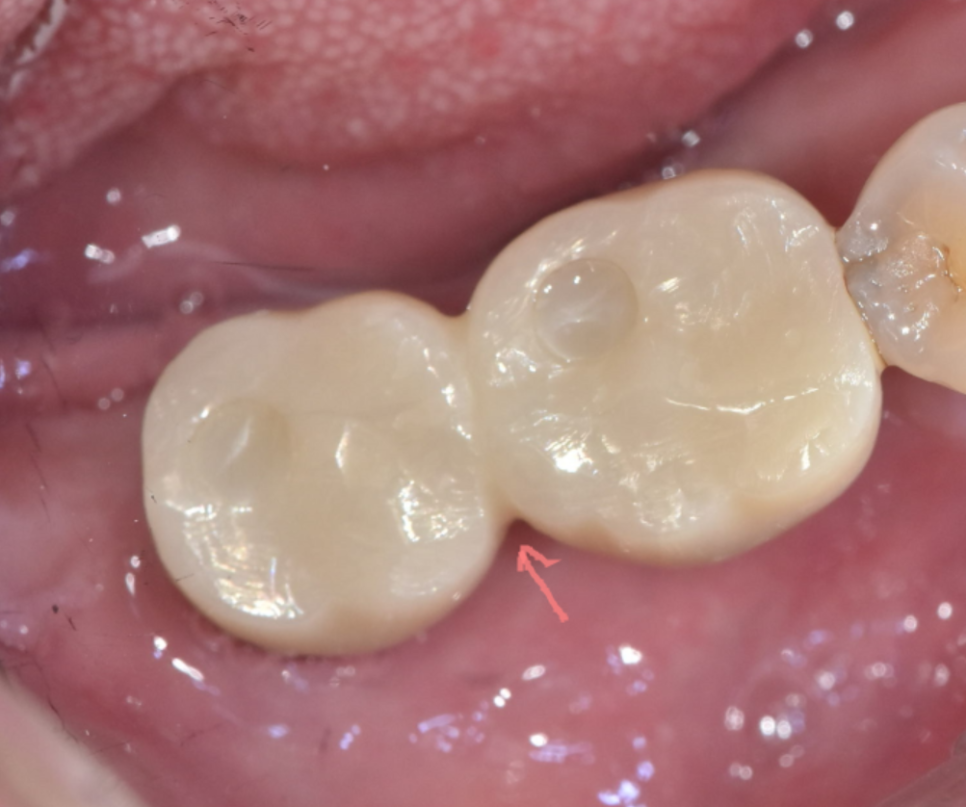

240830 임플란트 보철 주변으로 낀 찌꺼기와 잇몸이 빨갛게 부은 모습

-

냄새와 함께 잇몸 붓기, 피, 고름이 보인다